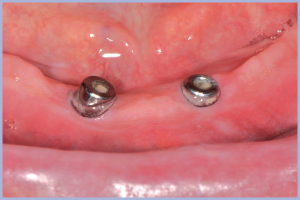

Dopo 3 mesi (durante i quali il paziente ha sempre portato la sua vecchia protesi ribasata in resina morbida) vengono scoperti gli impianti e messi i tappi di guarigione (Fig. 5).

- Fig. 5 – Situazione clinica al termine del condizionamento dei tessuti molli con i tappi di guarigione